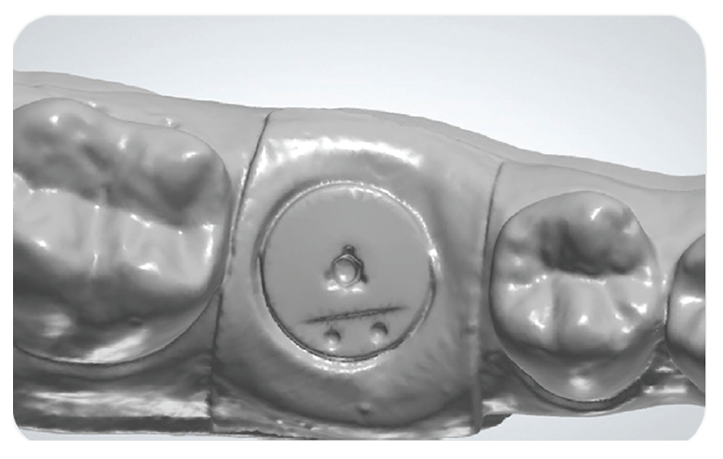

The 3-in-1 healing abutment, scan-body and impression coping for natural tissue-healing and restorative efficiency.

Encode Emergence technology provides more natural tissue healing for great aesthetics, and easy scanning and impressioning for workflow efficiency.

Enhanced Aesthetic Outcomes: The pink matte appearance closely matches the gingiva’s color, providing superior aesthetics and reducing intraoral scan reflection for clearer scan images.

Easy, efficient and proven Encode technology with contemporary emergence profile designs, intuitive codes and pink matte appearance.

Take a Digital or Traditional Impression

Intraoral Scanning

Traditional PVS Impression